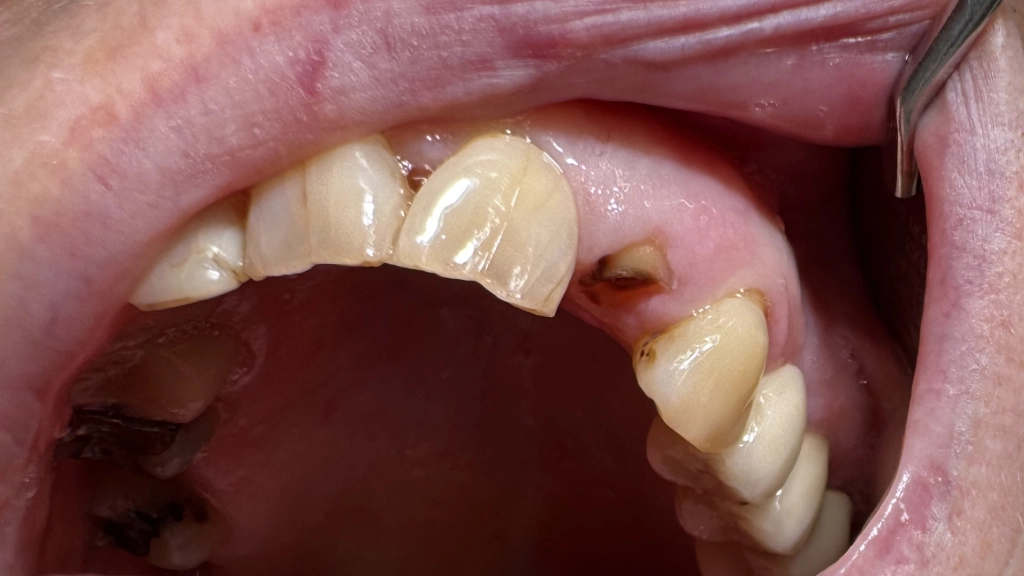

Het probleem

Je zit een lekker broodje te eten en die zwaar gevulde voortand breekt af, geen leuk zicht! Helaas is er te weinig tandmateriaal voor een kroon... Je staat nog midden in het leven: de levensduur van een brug (15 jaar gemiddeld) vind je terecht te kort. Daarnaast worden de (bijna) gave buurtanden bij een brug beschadigd: er moeten immers kronen op. Daarvoor wordt 1-1.5mm van je kostbare glazuur weggeboord. Een uitneembaar plaatje is goedkoper, maar hierdoor wordt je verhemelte bedekt. Eten smaakt minder en dat losse verhemelte? Nee.

Hier zie je hoe we de symmetrische tand gebruikt hebben als model. De uiteindelijke vorm wordt door de tandtechnieker ontworpen als de kunstwortel daar aan toe is.